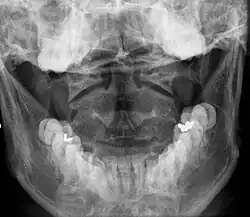

Once there is an onset of the symptoms in the patient, the patients are screened through cervical-spinal imaging techniques: X-ray, CT, MRI. [1] The scanning technique points out any cervical vertebrae defects and misalignments. (Image 1. and 2.) When cervicocranial syndrome is caused as a result of a genetic disease, then family history and genetic testing aid in making an accurate diagnosis of cervicocranial syndrome.